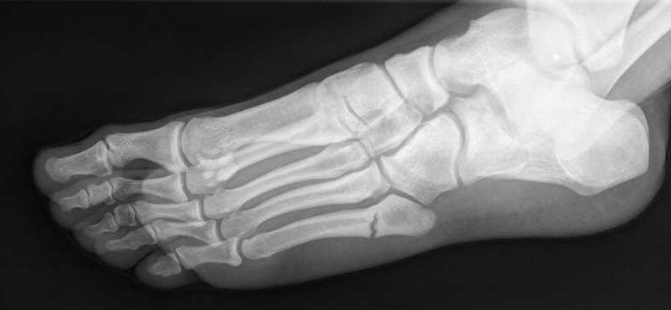

En estos casos, el diagnóstico de fractura del 5 Metatarsiano se basará, principalmente, en las pruebas de imagen, concretamente, en la Radiografía, aunque también tendremos que tener en cuenta la evaluación clínica para saber de qué manera se ha producido la lesión. Por otro lado, las pruebas adicionales, como puede ser la Resonancia Magnética, nos van a ayudar a evaluar la gravedad de la lesión y a descartar otras lesiones más graves.